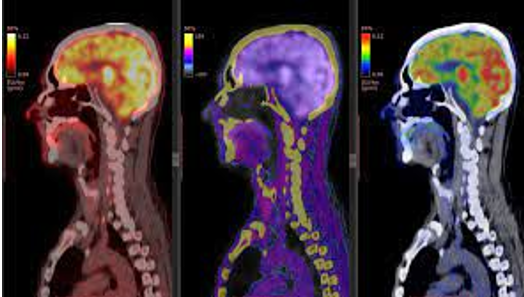

Máy cắt lớp điện toán phát xạ đơn photon (Single photon emission computed tomography – SPECT) là thiết bị chẩn đoán hình ảnh hạt nhân tiên tiến dùng để theo dõi phân bố thuốc phóng xạ trong cơ thể. Các đồng vị thường dùng là Iodine-131 (${}^{131}I$) để chẩn đoán và điều trị bệnh lý tuyến giáp, hoặc Technetium-99m (${}^{99m}Tc$) để khảo sát xương. Đồng vị ${}^{131}I$ phân rã $\beta^{-}$ và đồng thời phát ra tia gamma ($\gamma$) với chu kì bán rã là $T_{1} = 8,0197$ ngày.